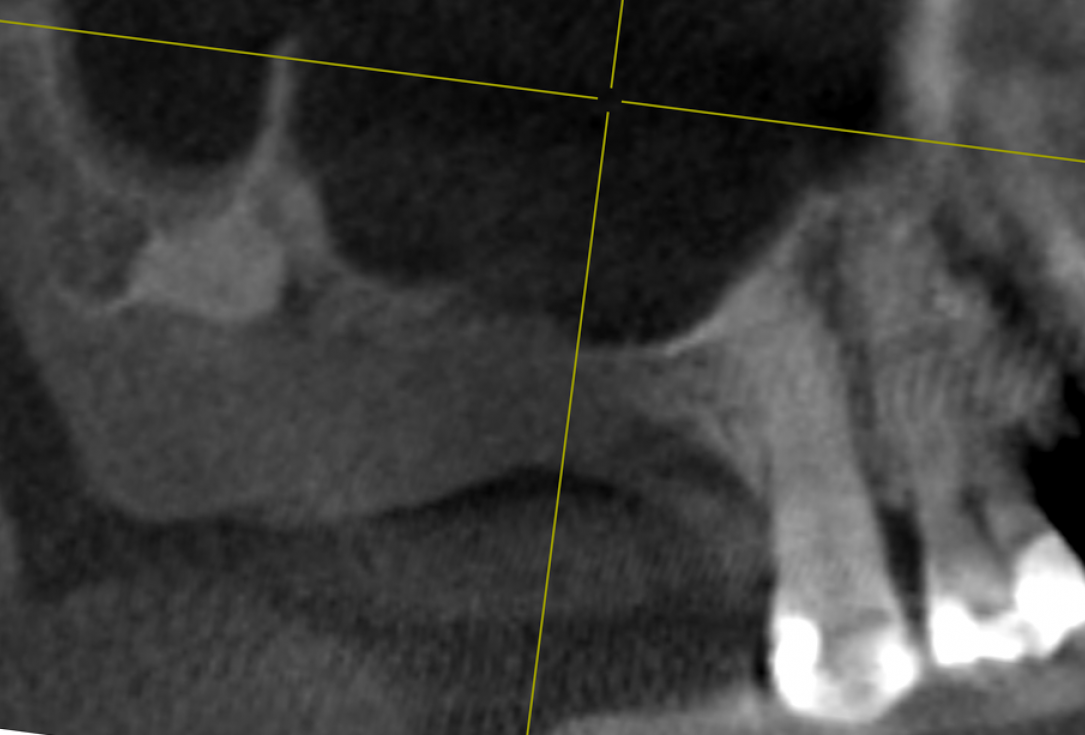

09/14 - Consolidation of graft material with minimal hyperplasia of sinus mucosa before implantation

Two-stage sinus lift with maxresorb® & collprotect® - Dr. S. Kistler